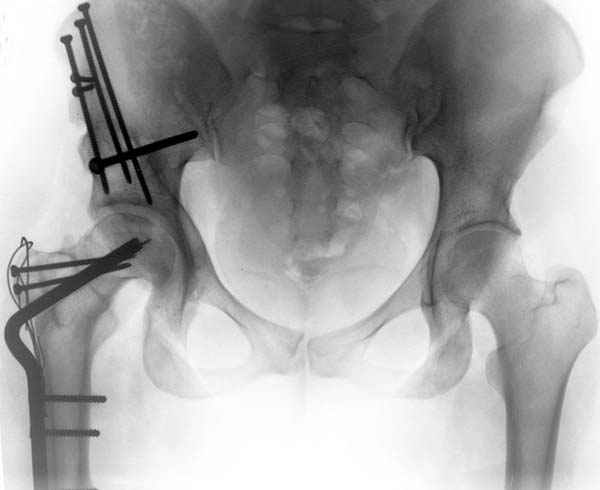

Рис.2 Та же трехмерная модель тазобедренного сустава без аналога связки головки бедра. Пружина динамометра удерживает тазовую часть модели от опрокидывания, поддерживая стабильность так же, как отводящие мышцы обеспечивают ее в отсутствии связки головки бедра.